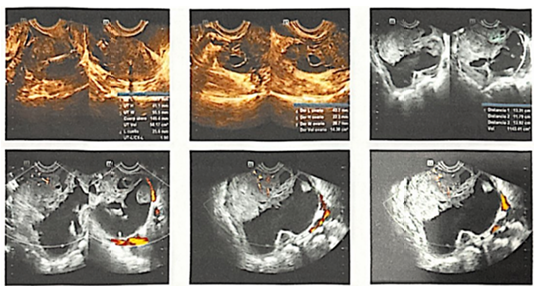

La paciente acudió con un cuadro de cuatro semanas de dolor pélvico constante, exacerbado con la bipedestación, sin flujo ni sangrado, y con sensación de inflamación pélvica. Al final de la cuarta semana, el dolor se intensificó irradiándose a la región umbilical. Durante la ultrasonografía pélvica ginecológica transvaginal (Figura 1), el ovario derecho mostró una apariencia anormal, reemplazado por una lesión multiloculada con más de 10 lóculos. La estructura sólido-quística de la lesión tenía un componente sólido que representaba aproximadamente el 70 % del tumor. Las proyecciones de la masa y el contorno de la lesión eran irregulares. El doppler color identificó una puntuación IOTA (International Ovarian Tumor Analysis) nivel III-IV, indicando una alta vascularización de la lesión. Las medidas del tumor fueron 133,1 x 117,9 x 139,2 mm, con un volumen de 1143,41 cm³. La clasificación O-RADS 5 (Ovarian Adnexal Imaging-Reporting-Data System) sugirió un alto riesgo de malignidad. Adicionalmente, se detectó líquido libre en el fondo de saco posterior, superior al útero y la lesión, consistente con ascitis.

Figura 1.Ultrasonografía pélvica ginecológica transvaginal.

En la ultrasonografía pélvica ginecológica transvaginal se observó que el ovario derecho presentaba lesión multiloculada, de estructura sólido-quística, representando aproximadamente el 70 % del tumor. Al utilizar el doppler color, se identificó una alta vascularización de la lesión, junto con las medidas del tumor y su volumen, lo que permitió clasificarla como O-RADS 5, lo que sugiere un alto riesgo de malignidad. Por otra parte, en la tomografía computarizada (TAC) de abdomen y pelvis con contraste se observó la presencia de ascitis en cantidad moderada sin evidencia de loculación, por lo anterior, la importancia de los métodos diagnósticos permitió establecer la necesidad de un abordaje quirúrgico y oncológico inmediato. Durante la cirugía se tomó líquido para análisis citológico, se liberaron adherencias, se hizo excéresis del útero y del tumor ovárico, enviándolo a patología para biopsia por congelación, arrojando un resultado positivo para cistoadenocarcinoma seroso papilar, el epiplón presentó metástasis focales por lo que se realizó linfadenectomía derecha y una omentectomía infracólica.